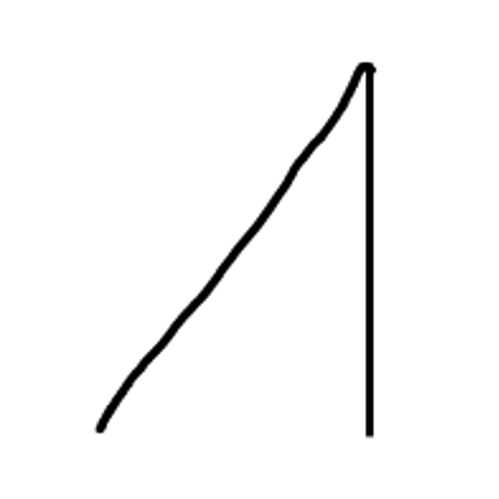

I overpack the cavity with amalgam. This allows easy carving and shaping. When I carve I try to imagine the cusps in three planes as shown below.